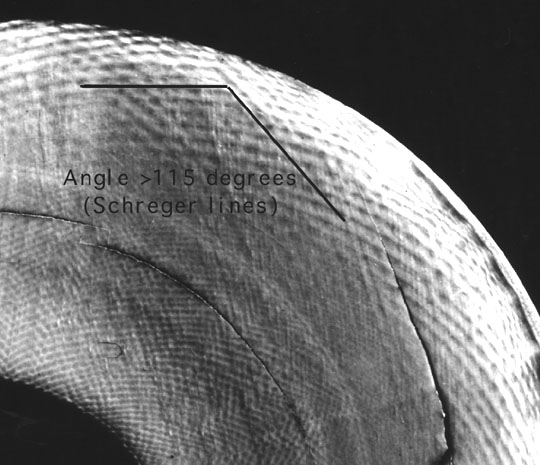

Cắt đứng dọc qua thân răng cửa

Lát cắt đứng dọc qua thân răng cửa

Các cấu trúc trong lát cắt dọc